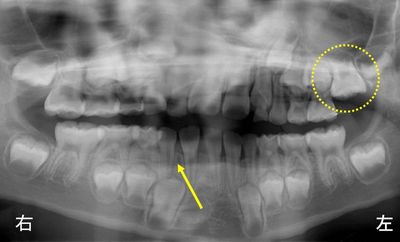

7歳の女の子、下あごの前歯が1本少ないと相談に来られました。レントゲン撮影したところ下あごの前歯(黄色矢印)が1本先天的にないことがわかりました(左上6歳臼歯の萌出が遅れています)。現在、下あごの前歯の部分は3本の永久歯が萌出している状態で、前歯が1本足りないので少し隙間が生じています。上下で歯の本数があっていないので、上あごの真ん中と下あごの真ん中がずれています。もし、下あごに4本の前歯があったとするとスペース不足のためにかなりガタガタの歯並びになっていたと思われます。しばらく経過観察を続けます。